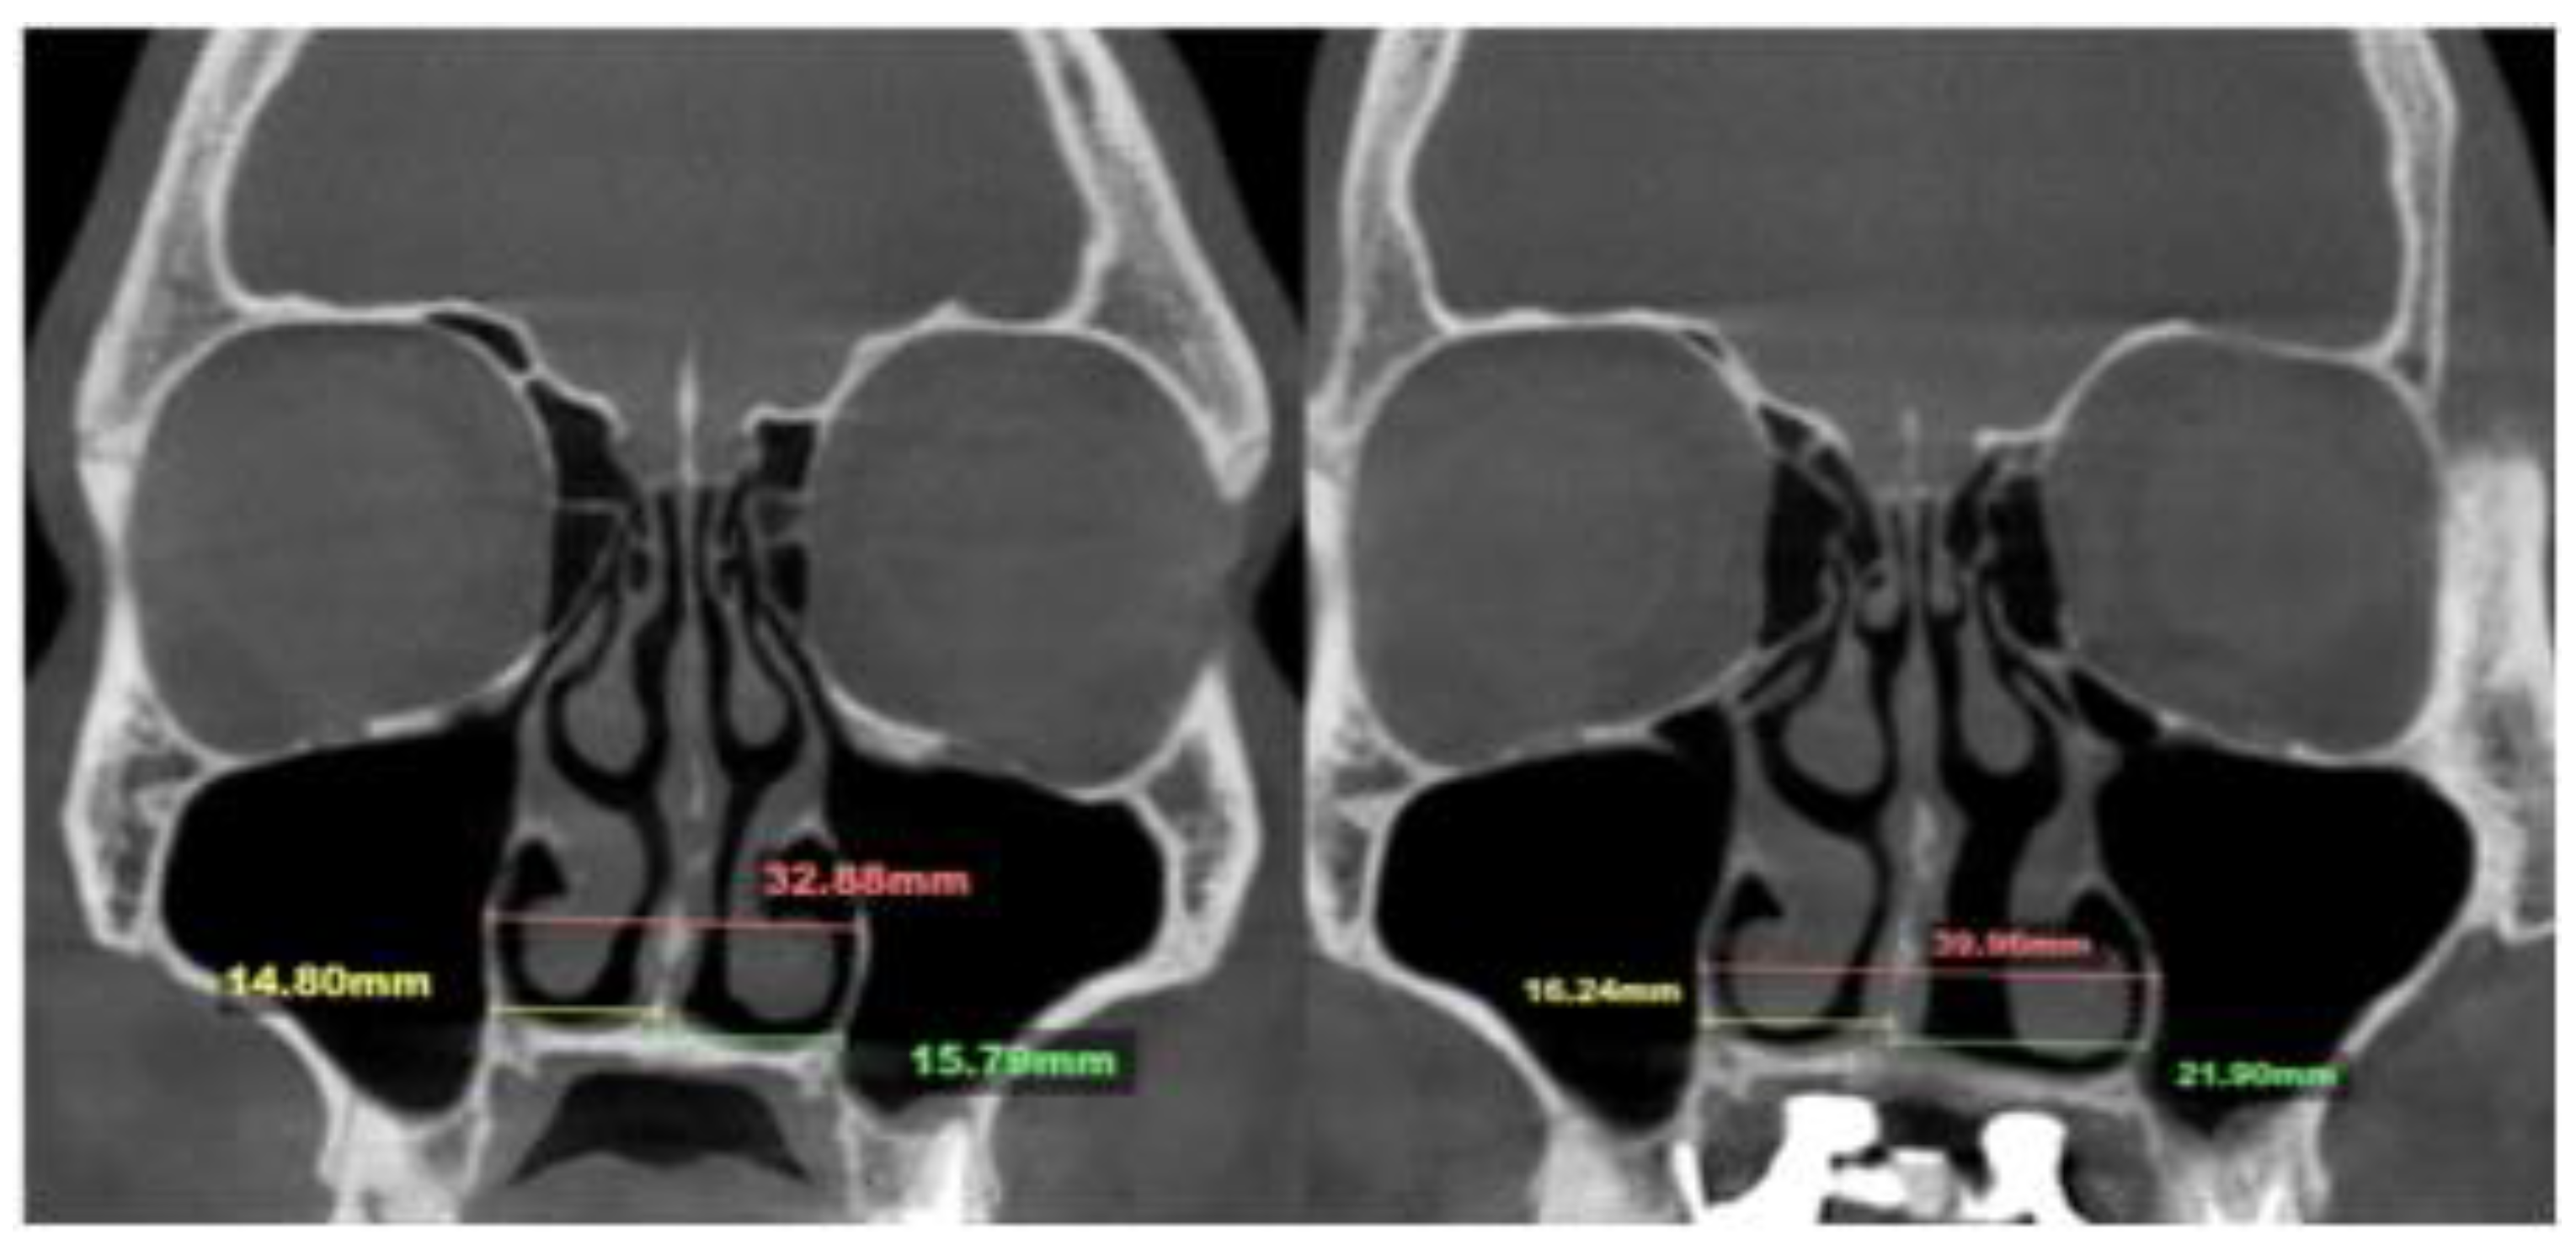

- Asymmetric expansion with residual attachment of the nasal septum unilaterally to the maxillary crestal bone (Figure 5,6);

- Diagonal fractures of the palatine bone extending from the distal margin of the palatal process of the maxillary bone unilaterally, often associated with pain and tension;

- Asymmetric displacement of the nasal base floor with unilateral downward and outward movement (Figure 5,6)

- Downward inclination and displacement of the alveolar process on the ipsilateral side (Figure 5,6);